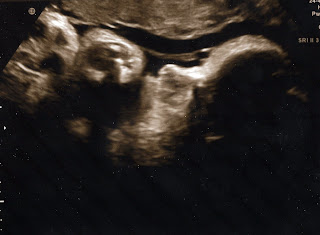

We watched Baby Wynne for a good 20 minutes while the tech took measurements and printed out some photos for us (the best ones are below). Baby Wynne mostly slept during the ultrasound, despite being awake all morning up till that point. As usual, he/she was a bit stubborn and faced away from us (toward my back) for most of our show, but then gave us a glimpse of the face near the end.

The tech was able to get a lot of good measurements and let us guess an estimated weight. At first, I said 20lbs (because I am feeling like poor Baby Wynne is squished in there!) and then I seriously guess 7lbs -- and was right on! Based mainly on measurements of Baby Wynne's belly and head, the tech is pretty confident that she/he weighs 7lbs. This is given with a +/- 1lb differential (meaning the baby could really weigh 6lbs or 8lbs), but the tech tried to convince us that she is usually right with her estimates.

So ... more than 3 weeks of growing left and Baby Wynne weighs 7lbs!!!

Based on these measurements, if Baby Wynne doesn't come on her/his own, it is likely we will be induced before the official due date (of January 11th).

| A more traditional ultrasounds shot of the left side of the face and some little hands! |